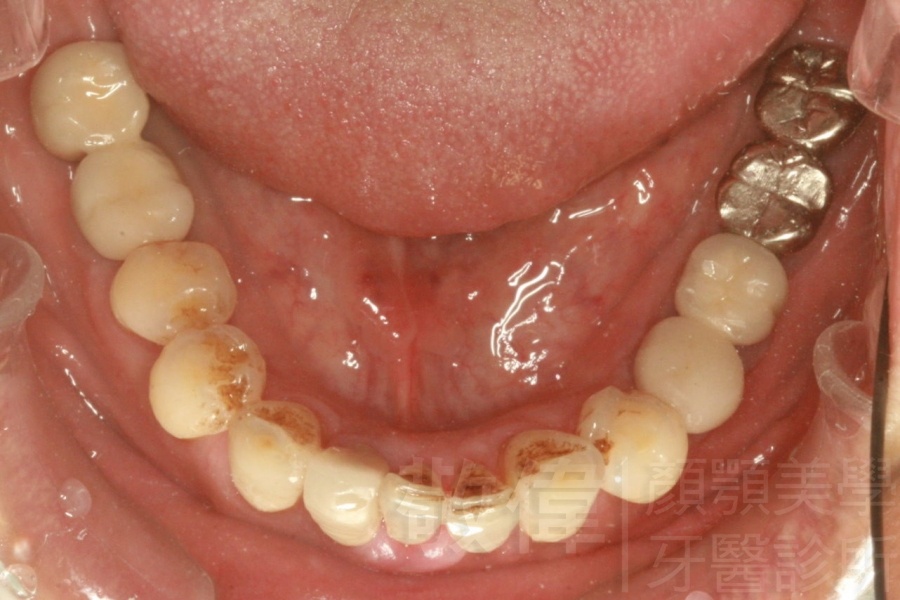

左下後牙區植牙後的支台柱   植牙後